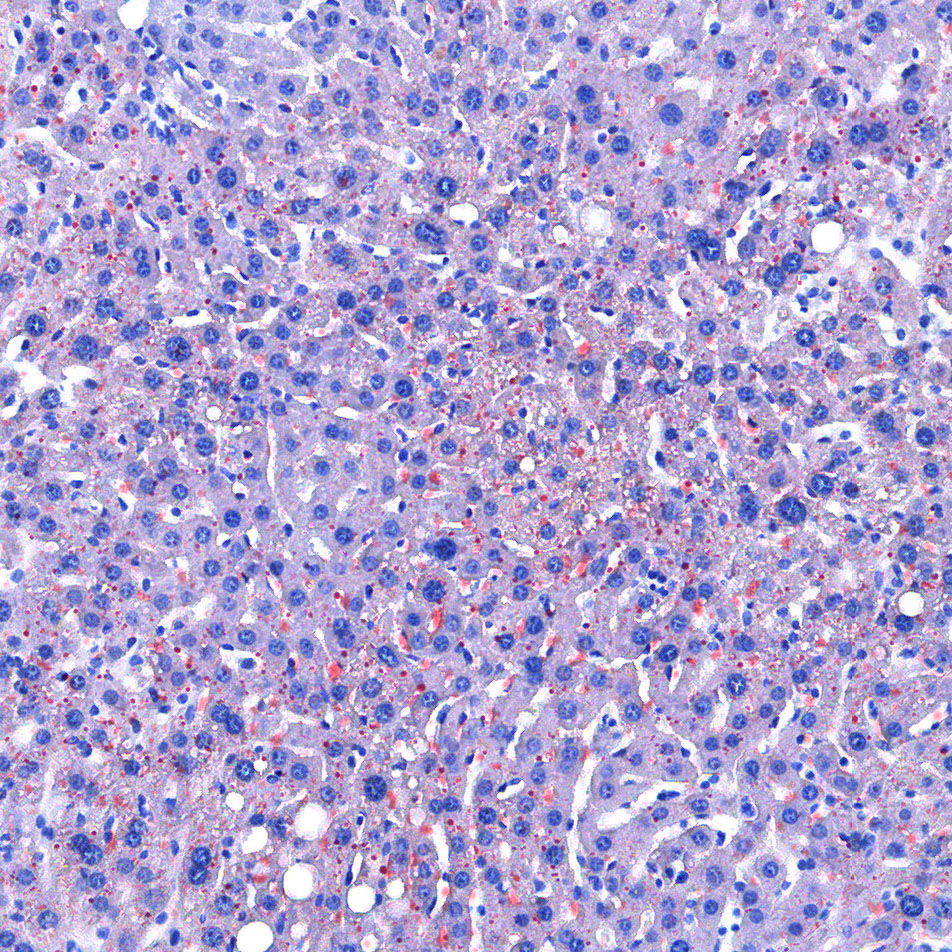

油红O对脂滴的染色机制一般认为是物理学上的溶液作用或吸附作用,借溶液作用使脂质染色,即油红O先溶于60%异丙醇中,然后切片浸入油红O染液中时,油红O在组织脂质的溶解度较60%异丙醇中的溶解度高,所以在染色时油红O从60%异丙醇中转移入脂质中使脂滴显示红色。

实验结果展示:

<油红O-肝>